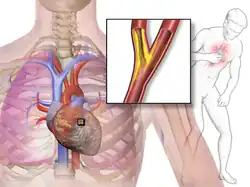

Die Angina pectoris[1][2] (Abkürzung AP; wörtlich „Brustenge“; Synonyme Stenokardie, sinngemäß „Herzenge“; veraltet Herzbräune, Brustbräune[3][4] und Herzbeklemmung) ist ein anfallsartiger Schmerz in der Brust, der durch eine Durchblutungsstörung des Herzens typischerweise im Rahmen einer koronaren Herzkrankheit (KHK) ausgelöst wird. Meist beruht diese auf einer Engstelle eines oder mehrerer Herzkranzgefäße. Angina pectoris ist also keine Krankheit, sondern ein Symptom bzw. die Bezeichnung für die klinischen Symptome einer akuten Koronarinsuffizienz. Medikamente zur Behandlung der Angina pectoris werden als Antianginosa bezeichnet.

Bei den meisten Patienten besteht eine Koronarsklerose, deren Zusammenhang mit der Angina pectoris Ende des 18. Jahrhunderts von Caleb Hillier Parry erstmals ausführlicher dargestellt wurde. Unter der Belastung kommt es zu einer Minderdurchblutung (Ischämie) des Gewebes und dadurch zu den typischen Symptomen. Eine Sonderform ist die Prinzmetal-Angina, hier wird eine vorübergehende Ischämie des Myokards durch einen Spasmus der Koronararterien ausgelöst. Die Dauer eines solchen Anfalls liegt zwischen Sekunden und Minuten. Auch das „Kardiale Syndrom X“ löst eine Angina pectoris aus.